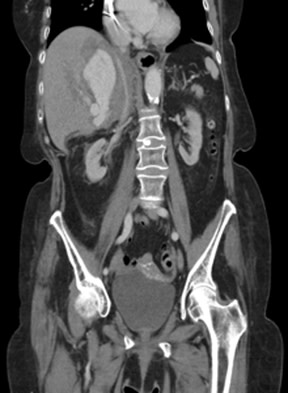

New study @AnnalsofIM bit.ly/2Km3KYu by @DrTalenfeld @WeillCornell: Percutaneous ablation for T1a #renalcancer has similar 5-year survival rates to radical nephrectomy but with far fewer 30-day complications and less #kidneyfailure.